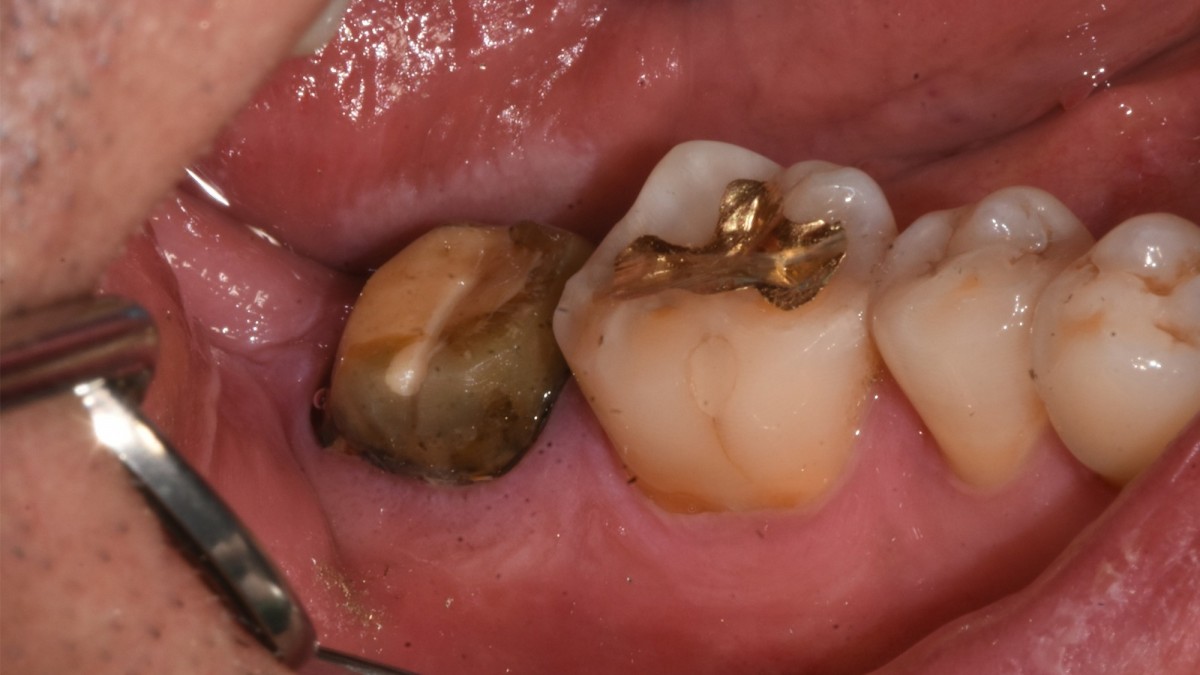

A 47-year-old male patient had a crown with an ill-fitting margin and crack-tooth syndrome in the lower 2nd molar. No systemic issue.